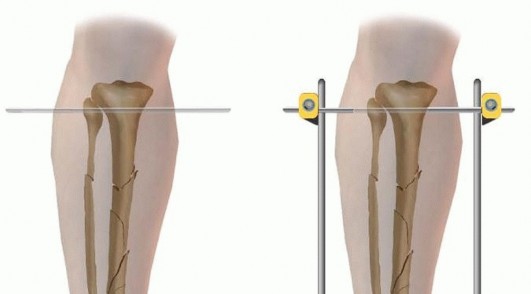

The stability of all monolateral fixators is based on the concept of a simple “four-pin frame.” Pin number, pin separation, and pin proximity to the fracture site, as well as bone bar distance and the diameter of the pins and connecting bars, all influence the final mechanical stability of the external fixator frame. 1 Large pin monolateral fixators rely on stiff pins for frame stability. On loading, these pins act as cantilevers and produce eccentric loading characteristics. Shear forces are regarded as inhibitory to fracture healing and bone formation, and this may be accentuated with pins placed in all the same orientation.

Monolateral Four-Pin Frame Application for Tibial Shaft Fracture Contemporary simple monolateral fixators have clamps that allow independent adjustments at each pin-bar interface, allowing wide variability in pin placement, which helps to avoid areas of soft tissue compromise. Because of this feature, simple four-pin placement may be random on either side of the fracture. ### Option 1 The initial two pins are first inserted as far away from the fracture line as possible in the proximal fracture segment and as distal as possible in the distal fracture segment ( TECH FIG 2A). A solitary connecting rod is attached close to the bone to increase the rigidity of the system. Longitudinal traction is applied and a gross reduction is achieved ( TECH FIG 2B-F). The intermediate pins can then be inserted using the pin fixation clamps attached to the rod to act as templates with drill sleeves as guides. These pins should not encroach on the open wound or severely contused skin in the immediate zone of injury. After placement of these two additional pins, the reduction can be achieved with minimal difficulty by additional manipulation of the fracture. Once satisfactory reduction has been accomplished, the clamps are tightened and reduction is confirmed via fluoroscopy. ### Option 2 Alternatively, all the fixation pins can be inserted independent of each other, with two pins proximally and two pins distally ( TECH FIG 3). The two proximal pins are connected to a solitary bar and the distal two pins are connected to a solitary bar. Both proximal and distal bars are then used as reduction tools to manipulate the fracture into alignment. Once reduction has been achieved, an additional bar-to-bar construct between the two fixed-pin couples is connected. Reduction is confirmed under fluoroscopy. 538